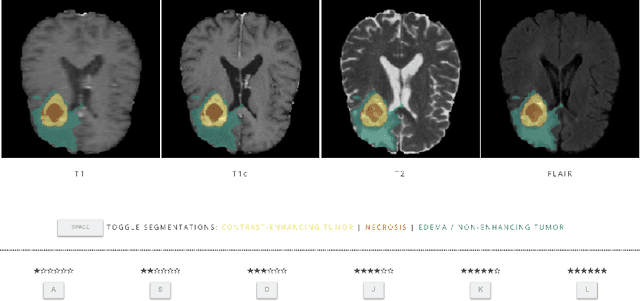

Abstract:In this study, we explore quantitative correlates of qualitative human expert perception. We discover that current quality metrics and loss functions, considered for biomedical image segmentation tasks, correlate moderately with segmentation quality assessment by experts, especially for small yet clinically relevant structures, such as the enhancing tumor in brain glioma. We propose a method employing classical statistics and experimental psychology to create complementary compound loss functions for modern deep learning methods, towards achieving a better fit with human quality assessment. When training a CNN for delineating adult brain tumor in MR images, all four proposed loss candidates outperform the established baselines on the clinically important and hardest to segment enhancing tumor label, while maintaining performance for other label channels.